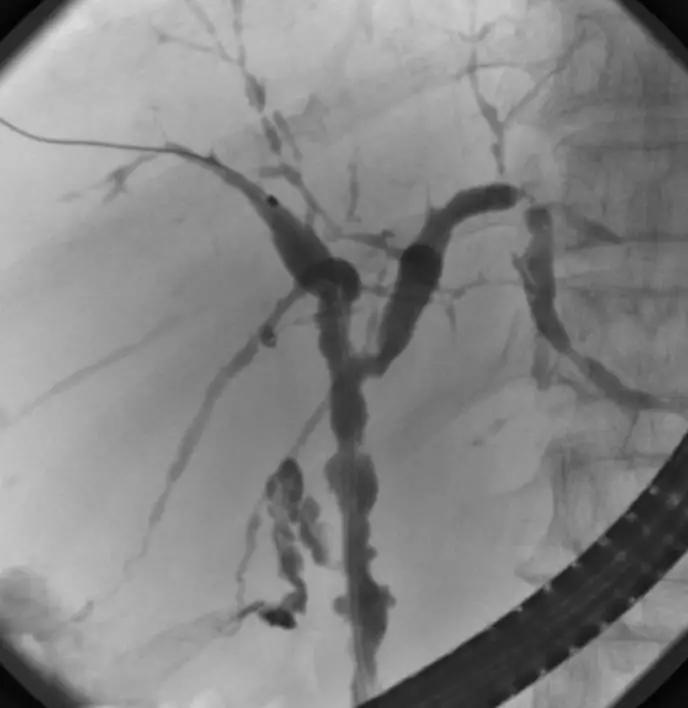

3、PSC影像学表现(日本厚生劳动省官网提供)

ERCP:胆管狭窄与扩张交互,呈串珠状改变

多发短小狭窄,胆管环状受累

PTCD:胆管呈边缘不整羽毛状

ERC:胆管壁呈憩室样突出